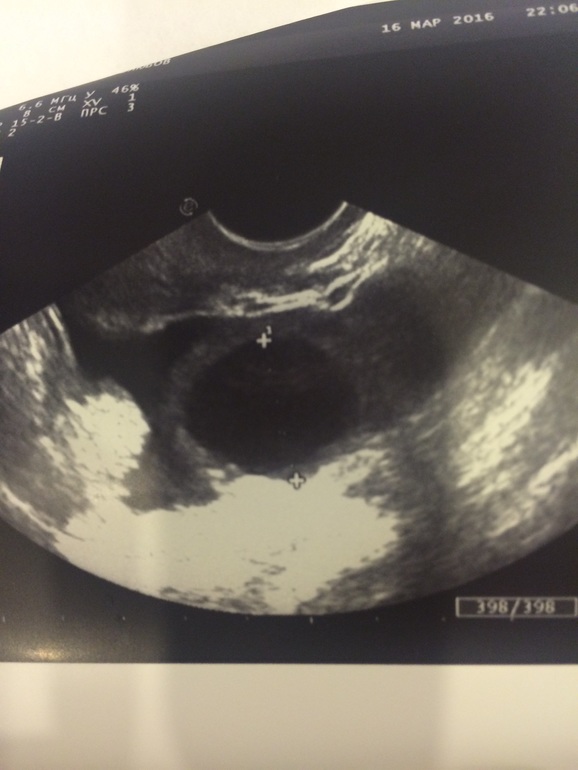

Что это?

Размер 22 мм.

Больше похоже на фолликул т.к контуры более чёткие, у ЖТ подругому и должна быть жидкость обязательно, кисты быть таких размеров не может, только свыше 25мм и то каждая из нас индивидуальна и эти так называемые "кисты" могут овулировать и в 30мм. Так что я думаю овулька должна случится вот-вот, ждите и прислушивайтесь к себе, может простреливать яичник или потягивать животик

Мне кажется больше на кисту похоже... обычно когда фол около него и другие видно, а тут такое ощущение что он один и всех подавил... хотя может проекция такая. Точно не жт у него края рваные должны быть

Был фолликул, я за следила за его ростом. Как это может быть киста? Размер 22 мм, то есть либо он вот-вот лопнет, либо регрессирует. Фолликулярная киста от 26 мм должен быть размер.

Вообще что можно сказать по одному снимку? Ни локализации ни размеров ( у объемных образований их 3). Я вижу округлое анэхогенное образование с четким ровным контуром и вроде бы дистальным усилением- киста скорее всего. Но я гинекологическим узи не занимаюсь.

Похож на фолликул! Круглый и ровный! У жт края неровные. Оно вообще на мой взгляд на лопнувший шарик похоже.

Фолликул. Свои помню как вчера. Желтое тело не ровное по краям и на узи похоже на цветочек.

Это ДФ, края ровные, он четко отделяется от окружающего рисунка, у желтого тела края не ровные и не четкие, и это не киста, так как она начинается с 25 и то не факт, да и то пишут пересистенция фолликула, но у меня фолликул с овулировал в 29